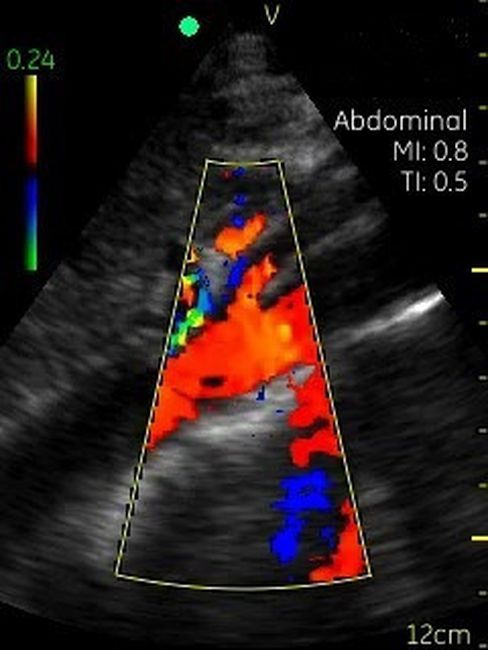

Невозможно было представить раньше, что УЗИ аппарат может помещаться на ладони руки человека. Теперь это реальность, воплощенная в корпусе и технологической начинке GE VSCAN. Инженеры заложили возможность получения дополнительной визуализации кровотока с цветной кодировкой в режиме реального времени для полноценной постановки диагноза на месте.

Визуализация Vscan:

· Наложение кровотока с цветовой кодировкой в реальном времени.

· Сектор цветного режима показывает кровоток с углом обзора 30 градусов

Цветовой допплер:

Да